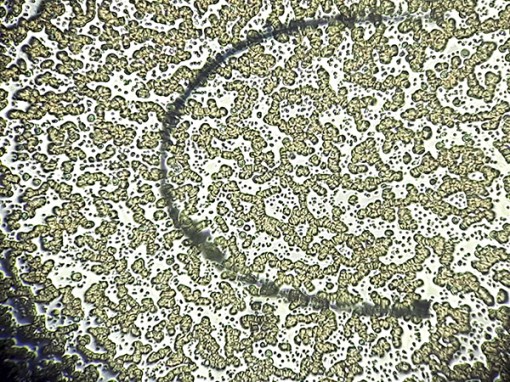

Báo động khủng hoảng sức khỏe sinh sản nam giới

Tình trạng béo phì, hút thuốc lá và phơi nhiễm hóa chất độc hại từ đồ nhựa là nguyên nhân chính khiến số lượng và chất lượng tinh trùng ở nam giới giảm nghiêm trọng. Đáng chú ý, tỷ lệ phái mạnh phải điều trị vô sinh đã tăng 700% chỉ sau 15 năm.